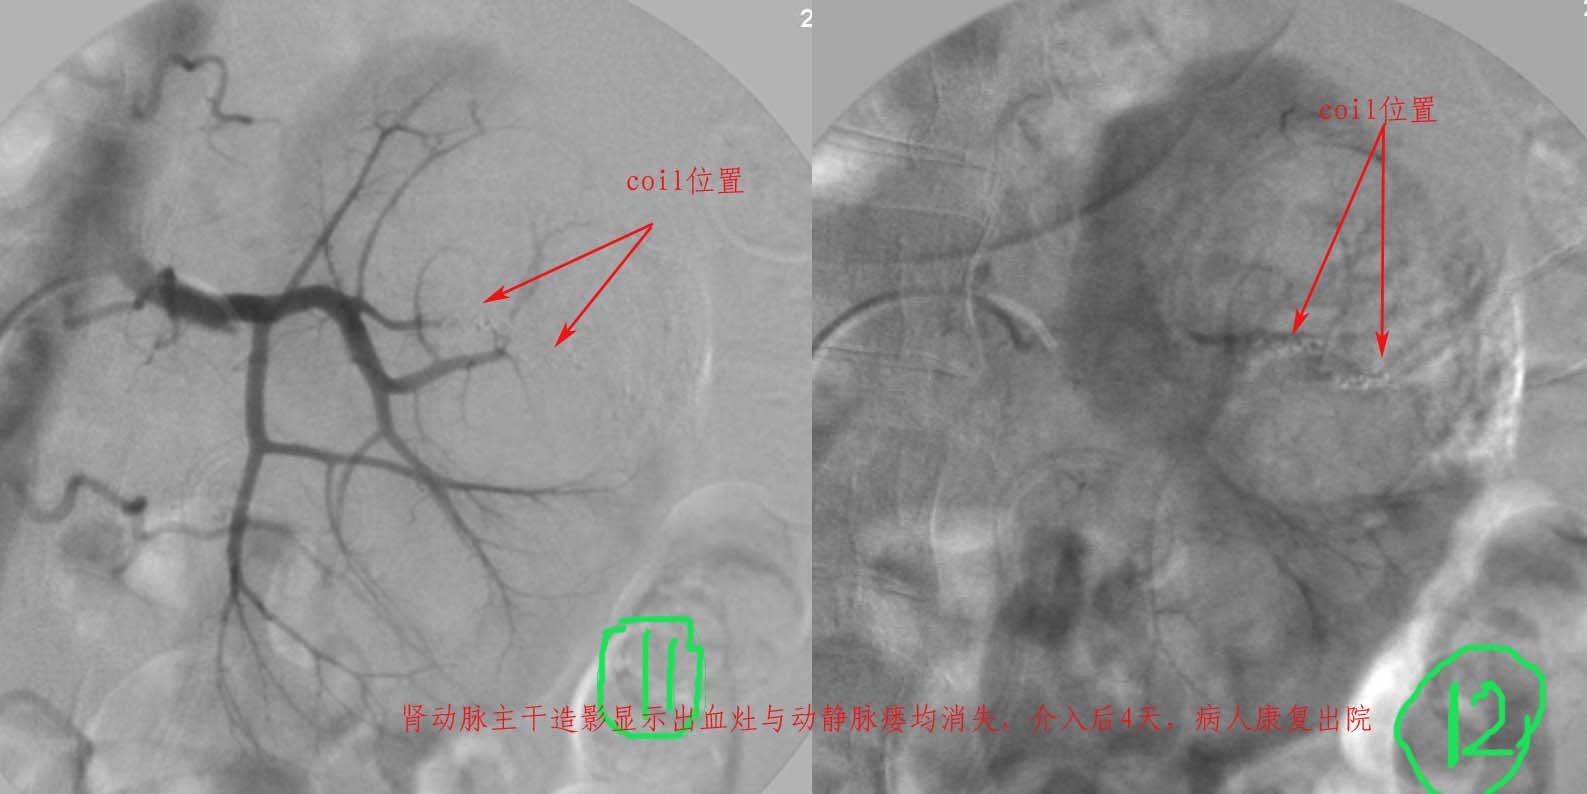

介入治疗过程:

注:图5\6文字标示应为".....再次证实出血部位"

准确的出血部位请参考\"介入治疗过程\"图片标示!